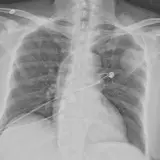

Over 2,100 interactive radiology cases, curated by radiologists for your level of training. Scroll, window, and view cases full screen — just like on PACS. Click linked findings in each writeup to jump straight to them on the image. Cases include sample reports, a focused discussion section, original illustrations, and videos.

PACSで期待されるツールを完備した完全インタラクティブな症例 — スクロール、ウィンドウ調整、ズーム、パン、計測、ROI、フルスクリーンモード。

重要な所見を症例画像上に直接ハイライトする豊富なアノテーション。症例解説内のリンクされた所見をクリックすると、スキャン上の正確な位置へジャンプできます。

職場のPACSステーションと同じようにスクロール、パン、ウィンドウ調整、ズームが可能

アノテーション付きの画像所見とイラストで効率的に学習